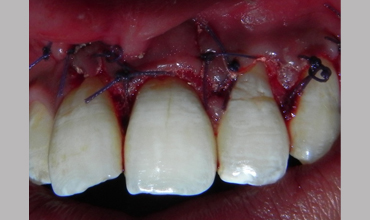

Surgical Management Of Large Periapical Cyst